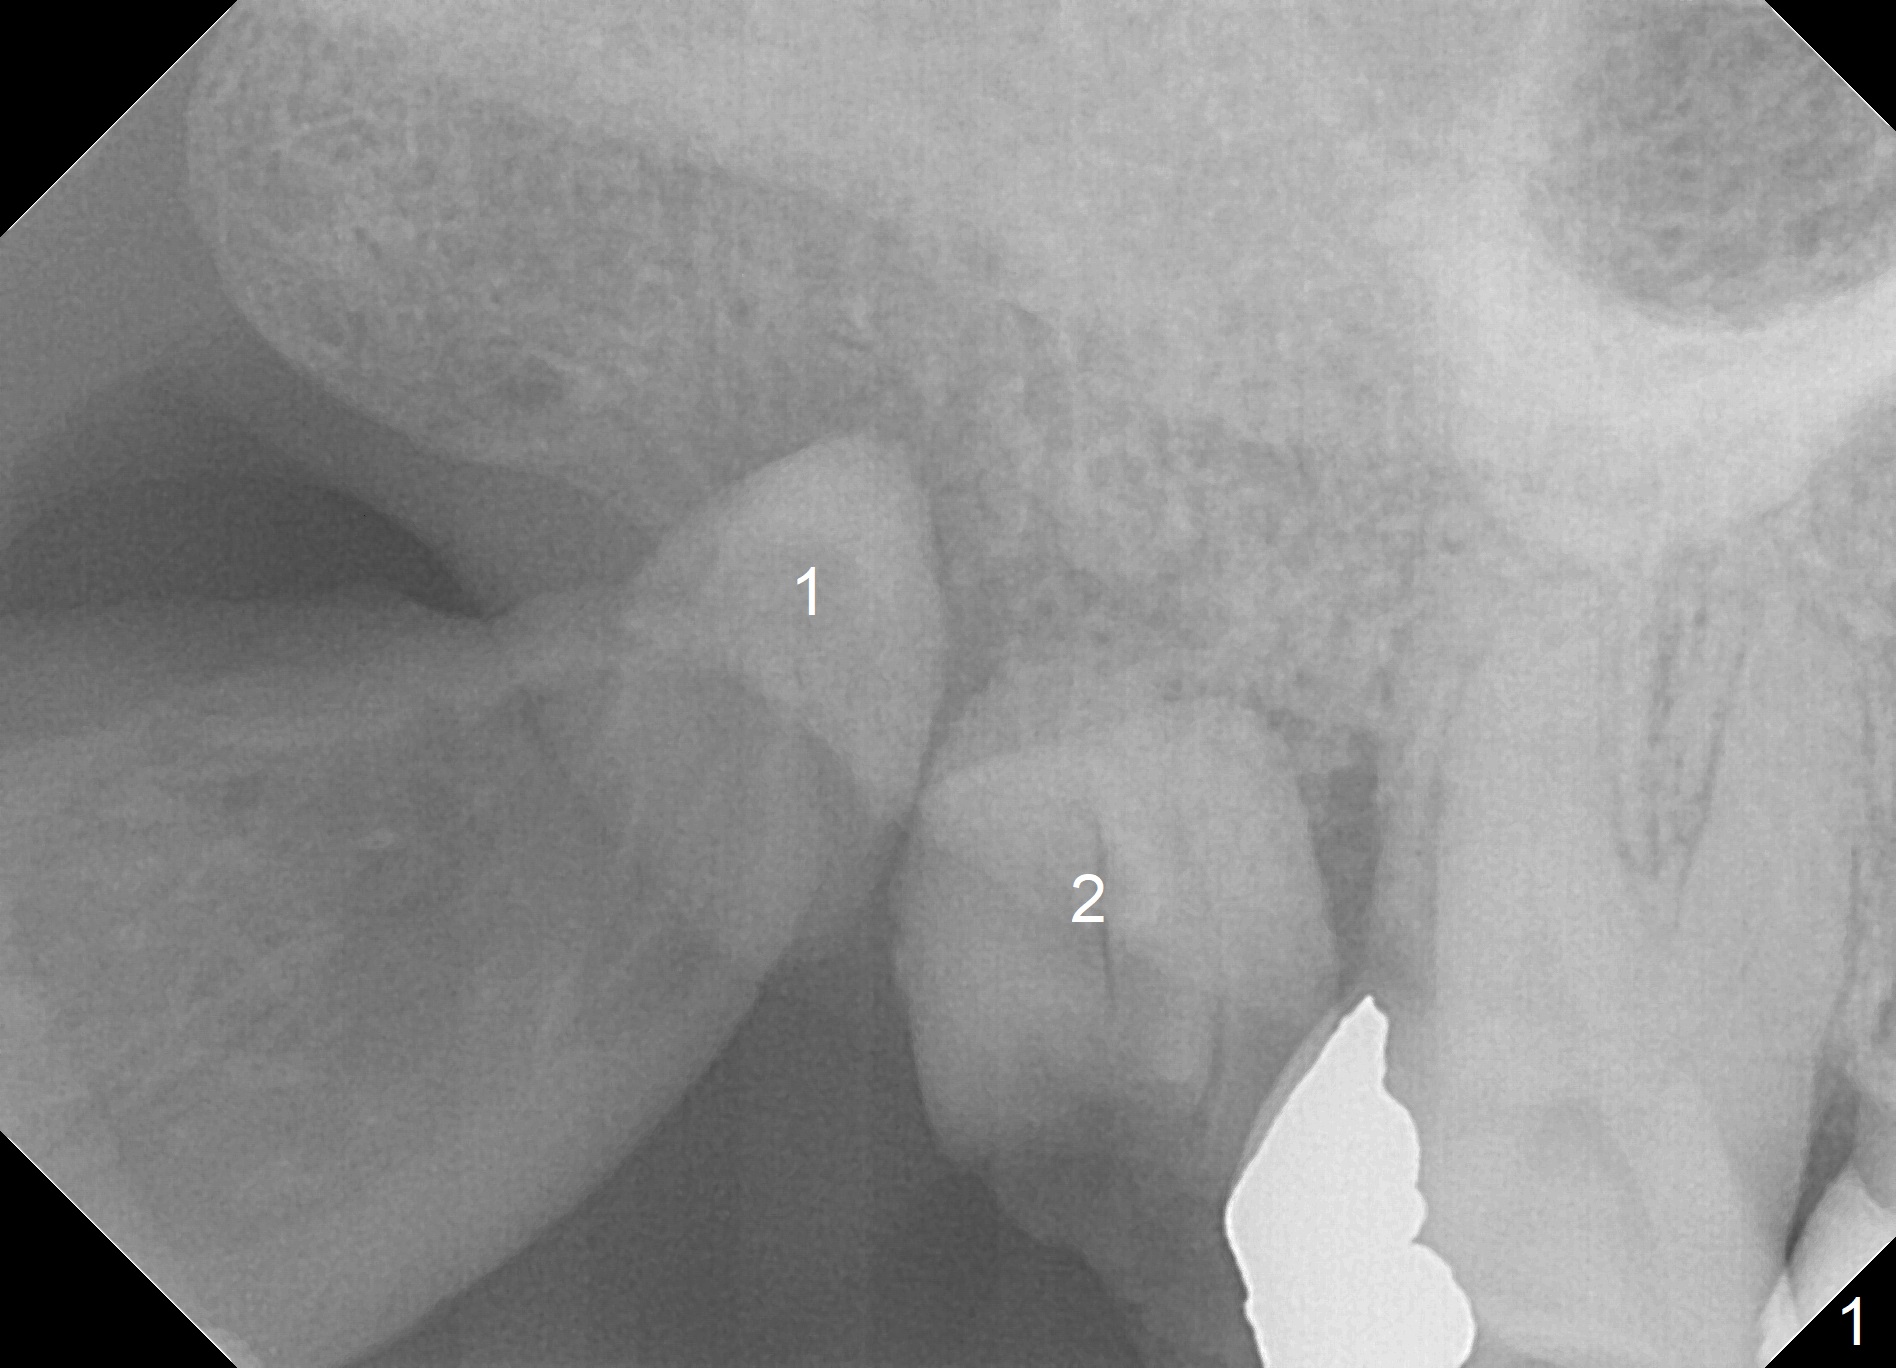

A 60-year-old woman requests extraction of the upper right 2nd and third molars and one implant (Fig.1). Although there is no problem of bone height, the intermaxillary vertical space is limited (data not shown). After implant (Fig.2) and abutment placement, the opposing tooth may need heavy reduction. Pay attention to implant trajectory so that a straight abutment will be used to avoid restorative complication (screw loosening).